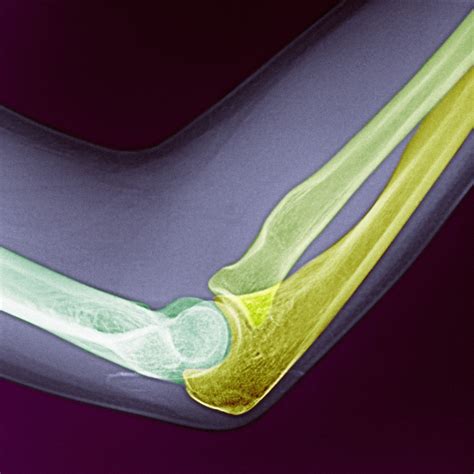

An elbow hairline fracture involves a small crack in one of the bones that make up the elbow joint. The elbow is a complex joint composed of three bones: the humerus (upper arm bone), the ulna (one of the forearm bones), and the radius (the other forearm bone). These bones are held together by ligaments, tendons, and muscles, which allow for a wide range of motion.

Hairline fractures are typically non-displaced, meaning the bone fragments remain in their normal position. This is in contrast to displaced fractures, where the bone fragments are separated and may require surgical intervention to realign.